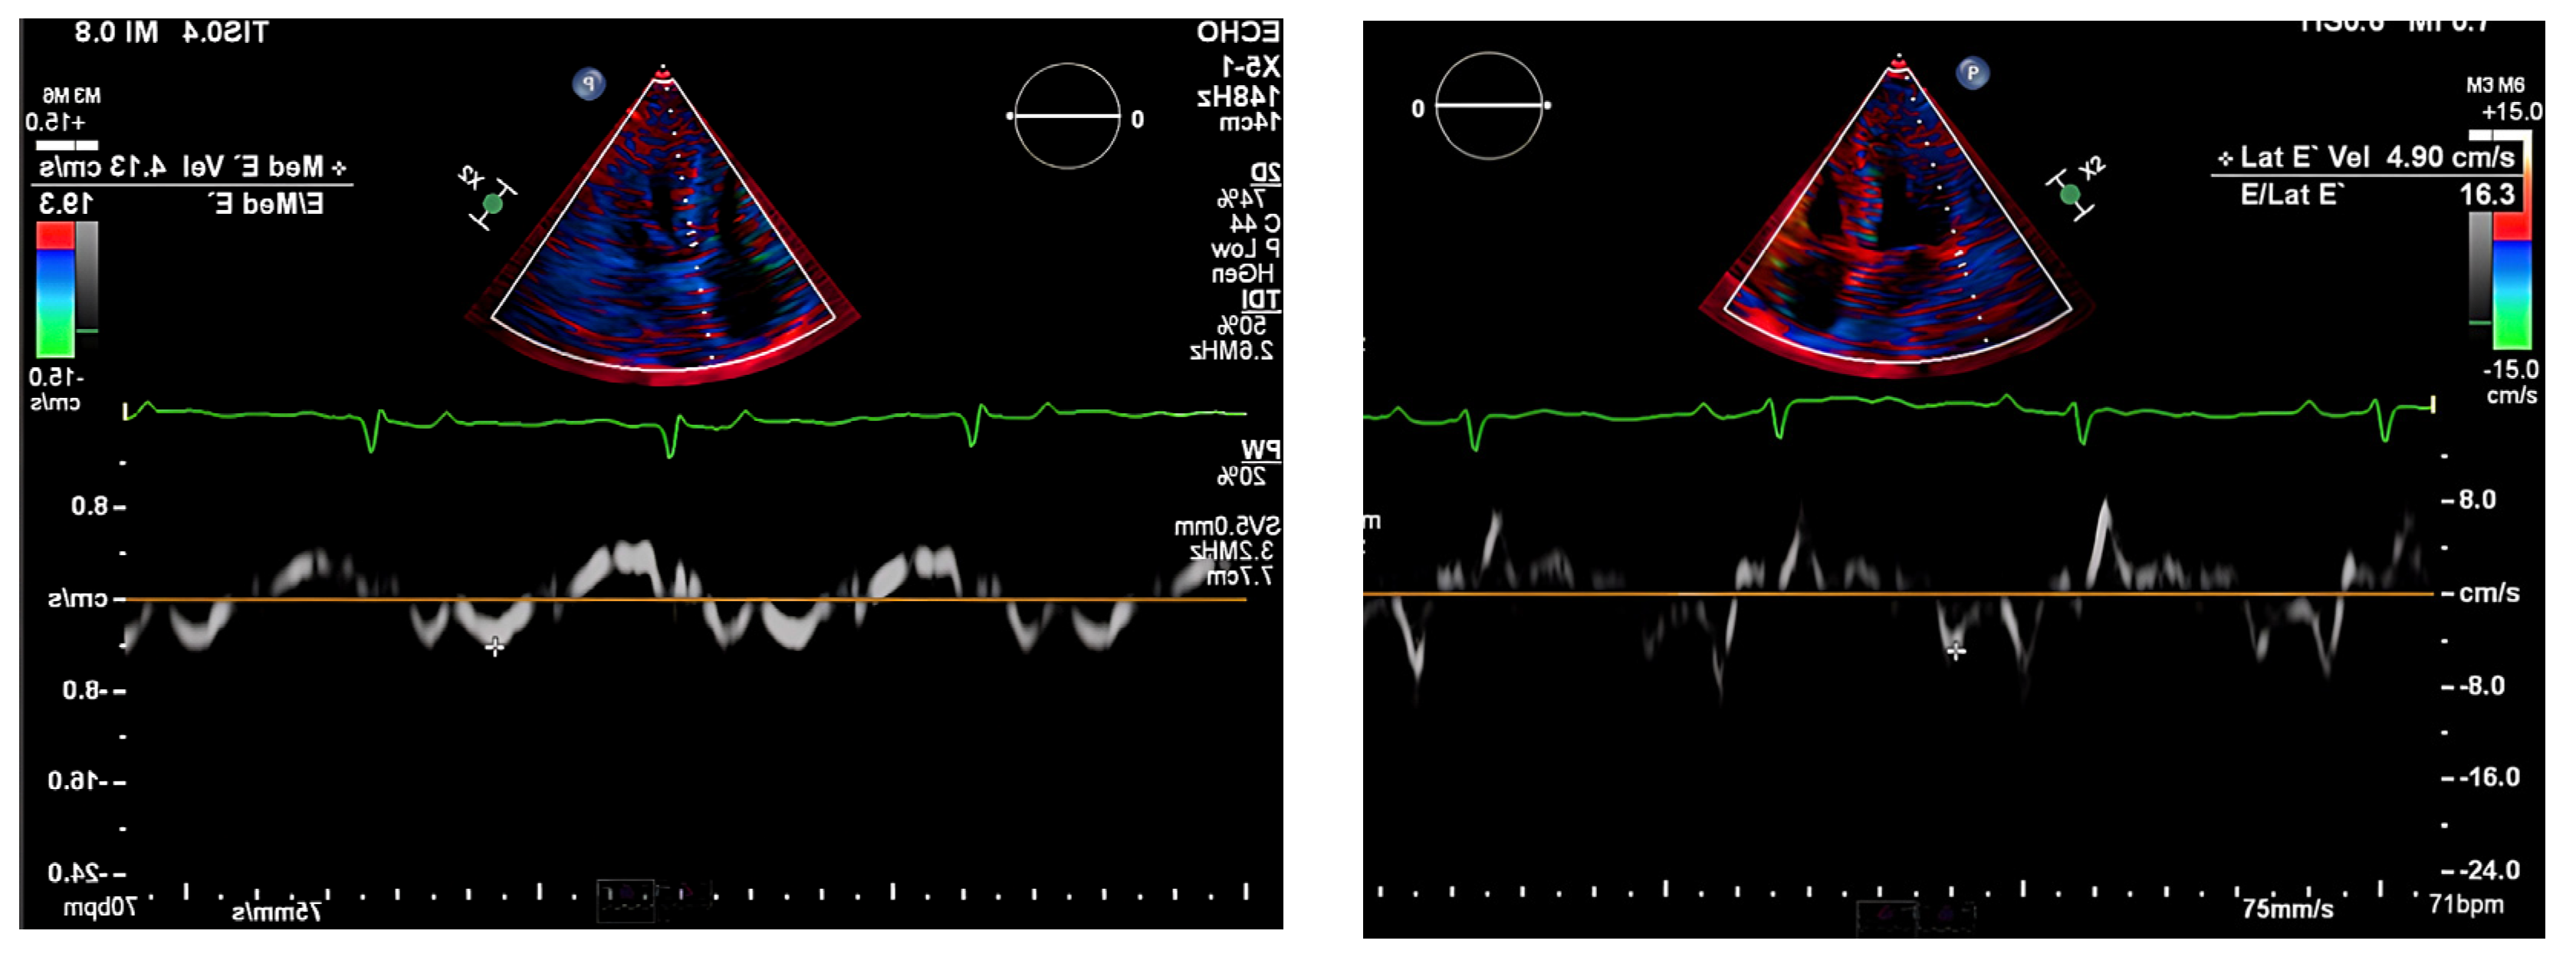

The chest radiograph did not show any acute findings. Electrocardiogram (ECG) (Figure 1) showed normal sinus rhythm with first-degree atrioventricular block, left axis deviation, and low voltage in limb leads. No prior echocardiogram (ECHO) was available, so an initial ECHO was obtained showing preserved ventricular ejection fraction (EF), moderate left ventricular hypertrophy (LVH), stage II diastolic dysfunction, and small pericardial effusion (Figure 2 and Figure 3).

Figure 3. Pulse-wave Tissue Doppler ECHO showing elevated E/E′ ratio and low mitral annulus velocities suggestive of diastolic dysfunction.